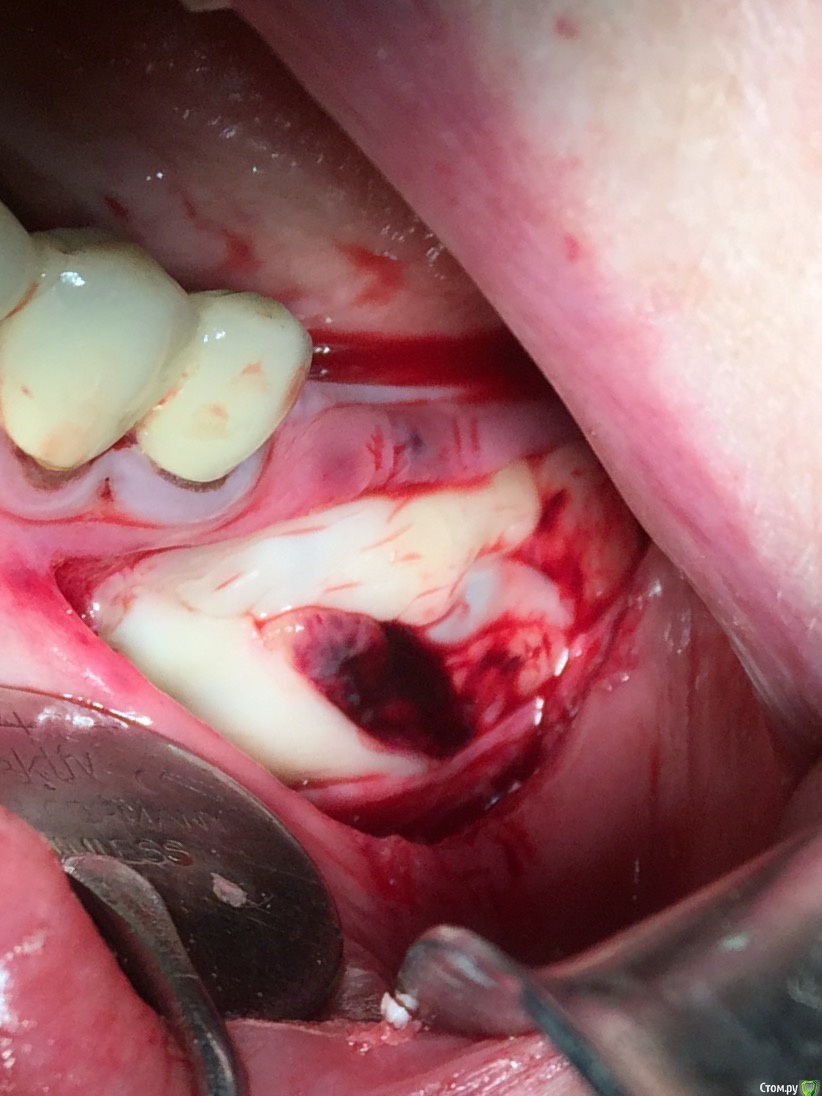

Глеб Митрофанов Опубликовано 16 января, 2016 Поделиться Опубликовано 16 января, 2016 Продолжение 13 Ссылка на комментарий

Глеб Митрофанов Опубликовано 16 января, 2016 Автор Поделиться Опубликовано 16 января, 2016 Скажите, пожалуйста, чем укрылись на 5-м фотоА-PRF Ссылка на комментарий

Глеб Митрофанов Опубликовано 16 января, 2016 Автор Поделиться Опубликовано 16 января, 2016 Что за блок вставлен ? SP-BLOCK osteobiol 1 Ссылка на комментарий